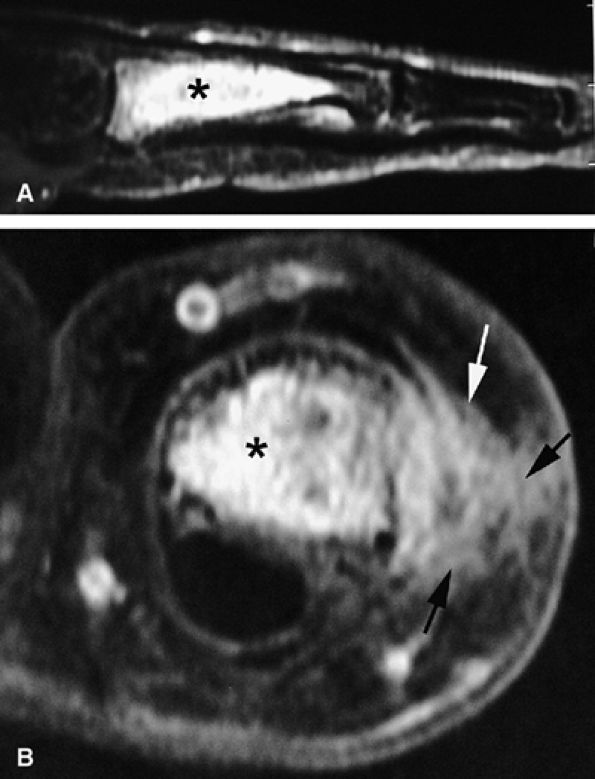

FIGURE 11.108 ● Axial anatomy of the nail unit. (A) Distal interphalangeal joint. (B) Matrix area. (C) Photomicrograph of the matrix area with hematoxylin and eosin staining. (D) Nail bed area. ET, extensor tendon; PNE, posterior nail fold; CL, collateral ligament; MP, middle phalanx; VP, volar plate; FDP, flexor digitorum tendon; MPL; matricophalangeal ligament; NR, nail root; PLNM, posterolateral corners of the nail matrix; SMA; submatrix area; DM; dorsal matrix; IM, intermediate matrix; DP, distal phalanx; P, pulp; LF, ligament of Flint; NBE, nail bed epithelium; NBC, nail bed corium; LNF, lateral nail fold; RU; rima ungualum.